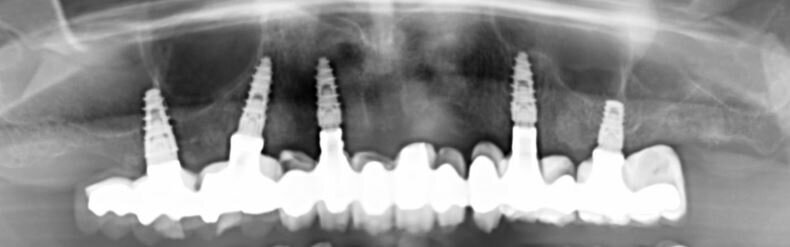

Fig. 7_Radiografia panoramica a tre anni dall’intervento in cui si apprezza il mantenimento dei livelli ossei peri-implantari.